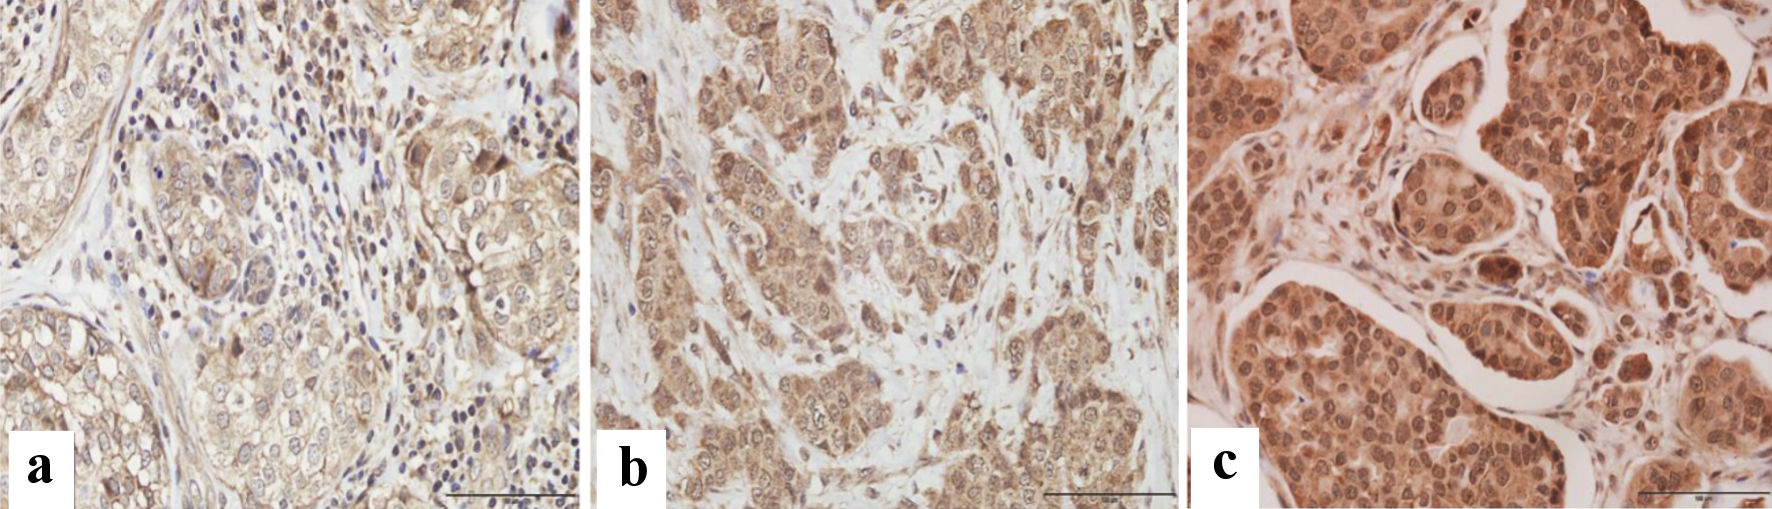

The immune reactive score (IRS) was evaluated using a semi-quantitative approach based on staining intensity (SI) and percentage of positively stained cells (PP) for the evaluation of VDR protein. For each sample, IRS = SI × PP [15]. VDR intensity was scored as follows: 0: no staining, 1: weakly positive, 2: moderately positive, and 3: strongly positive. The scoring of the staining pattern was based on the percentage of positively stained cells: 0: 0%, 1: < 10%, 2: 10-50%, 3: 50-80% and 4: > 80%. The IRS final score thus ranged from 0 to 12, designated as weak for a score of 0 to 3, and strong for a score of 4 to 12. Scoring was based on the color as positive showed brown and negative showed blue/purple (Fig. 1).

![]() Click for large image | Figure 1. Immunohistochemical assessment of VDR expression in paraffin-embedded breast cancer tissues. Microscopic images showing various degrees of intensity: (a) mild, (b) moderate, and (c) strong VDR expression. Images were captured at × 400 magnification, with a scale bar representing 100 µm. |